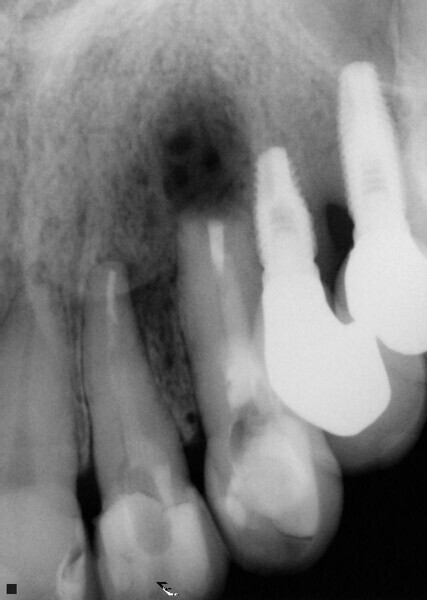

Fig. 1: A cone beam computed tomography was performed for diagnosis and to establish a treatment plan. (Photos/Provided by Renato Interliche, Douglas Giordani Negreiros Cortez and Clauber Romagnoli)